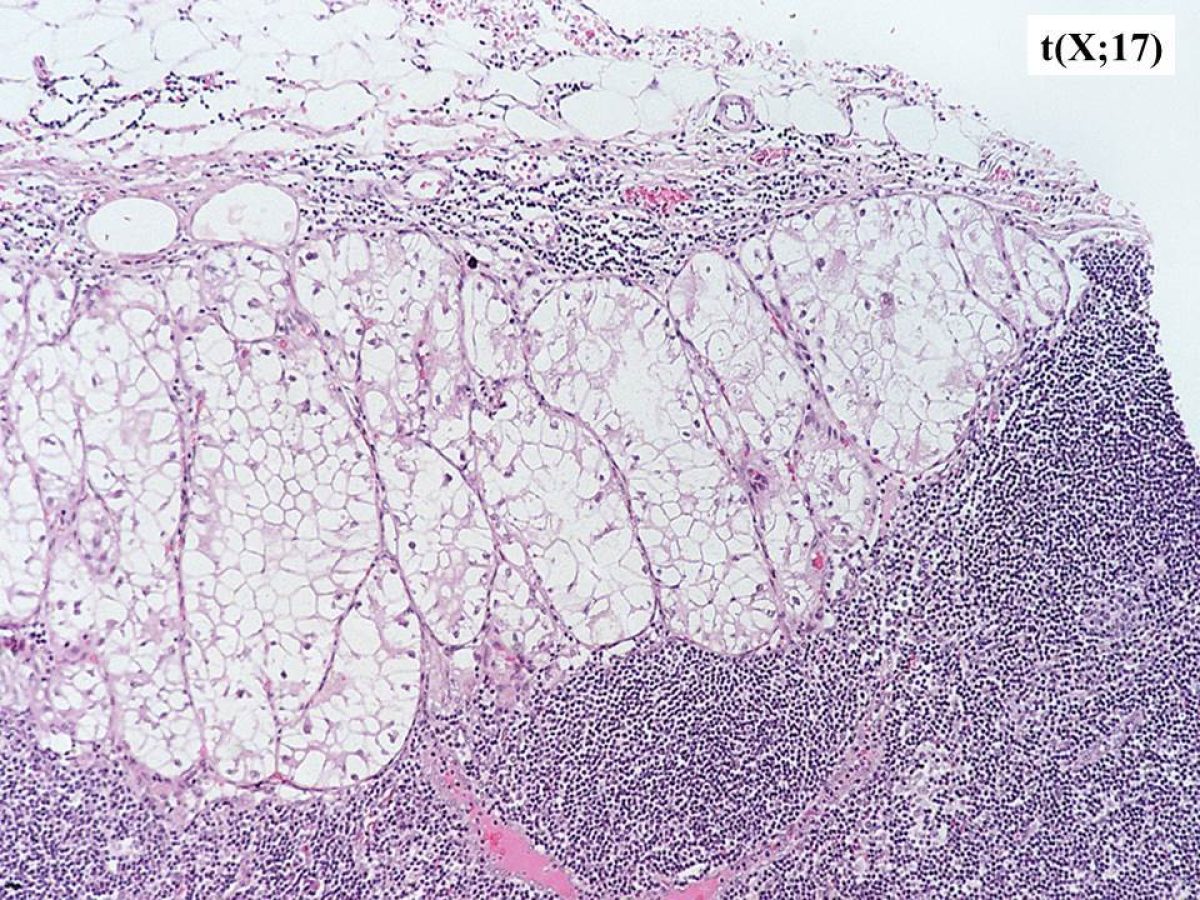

These pathology images are examples of what Translocation Renal Cell Carcinomas look like under the microscope.